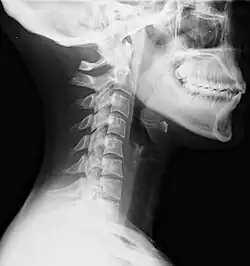

Lateral view X-ray of whiplash showing a loss of normal lordosis of the cervical vertebrae